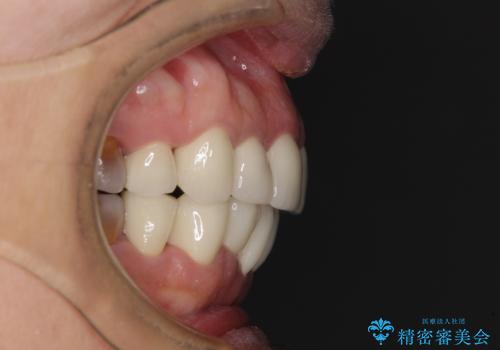

- 小さいころからの歯の変色と矯正治療の後戻りを気にして来院された患者様です。

気になる変色歯を仮歯に変え、その後歯列不正を矯正治療で改善し、最後にオールセラミッククラウンにて補綴治療することとしました。